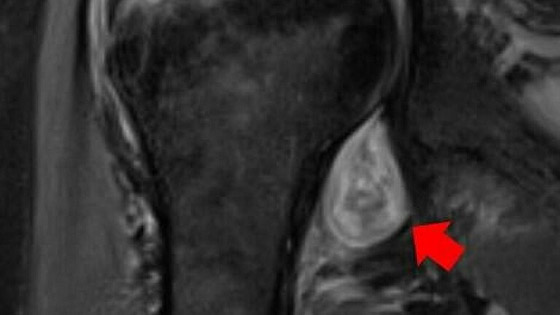

وقد أجرى باحثون من جامعة نورث وسترن الأمريكية بالتعاون مع أطباء من شبكة مستشفيات Northwestern Medicine ، دراسة شملت المرضى الذين رقدوا في المستشفى خلال أشهر مايو-ديسمبر 2020، الذين ظهرت عندهم أعراض "غريبة" خلال مرضهم أو بعد شفائهم، ما أجبرهم على استشارة أطباء أخصائيين. واستخدم الباحثون في فحص هؤلاء المرضى التصوير المقطعي بالكمبيوتر، والتصوير بالرنين المغناطيسي والموجات فوق الصوتية، ووجدوا أن الأعراض "الغريبة" بعد المرض، مرتبطة برد فعل المناعة الذاتية للجسم.

ويضيف ديشموخ، من أجل تشخيص أكثر دقة يجب استخدام طرق التصوير الحديثة، ويقول، "تسمح لنا الصور، بتمييز الألم البسيط في الجسم الذي يلاحظ في  حالة الإصابة بالإنفلونزا ، عن ألم العضلات والمفاصل الناتج عن الإصابة بمرض "كوفيد-19". حتى أن الخبراء يمكنهم في بعض الحالات استنادا إلى هذه الصور تشخيص إصابة الشخص بـ "كوفيد-19" إذا لم تظهر عليه أعراض المرض ولم يشعر بإصابته". ويشير الباحثون، إلى أن الطرق الشعاعية، تسمح باكتشاف مختلف التكوينات: الوذمة، تغيرات التهابية في النسجة، وجود السوائل والأورام، والأورام الدموية، والأنسجة الميتة التي تشير إلى بداية الغنغرينا.